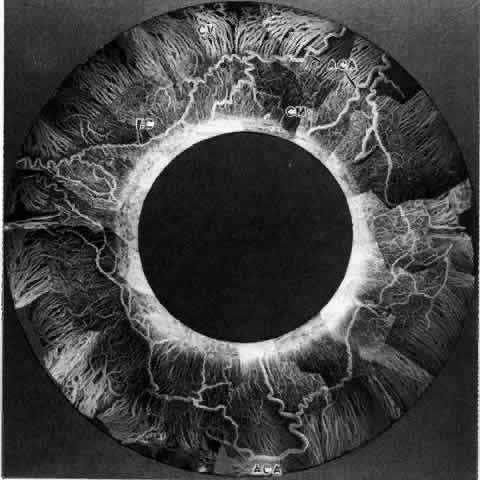

not be performed. Scleritis usually affects the anterior segment of the eye, possibly because

this is the area with the best blood supply, but with sluggish flow

through the vessels (Fig. 19). The sclera is thickened and roughened in the affected area, which appears

can be mistaken for malignant melanoma.  Fig. 19. Anterior necrotizing scleritis. The eye was removed because of loss of

vision and intractable pain. No form of steroid was given to this patient

because of a severe Pseudomonas infection of the chest. (Courtesy of Professor N. Ashton) Fig. 19. Anterior necrotizing scleritis. The eye was removed because of loss of

vision and intractable pain. No form of steroid was given to this patient

because of a severe Pseudomonas infection of the chest. (Courtesy of Professor N. Ashton)